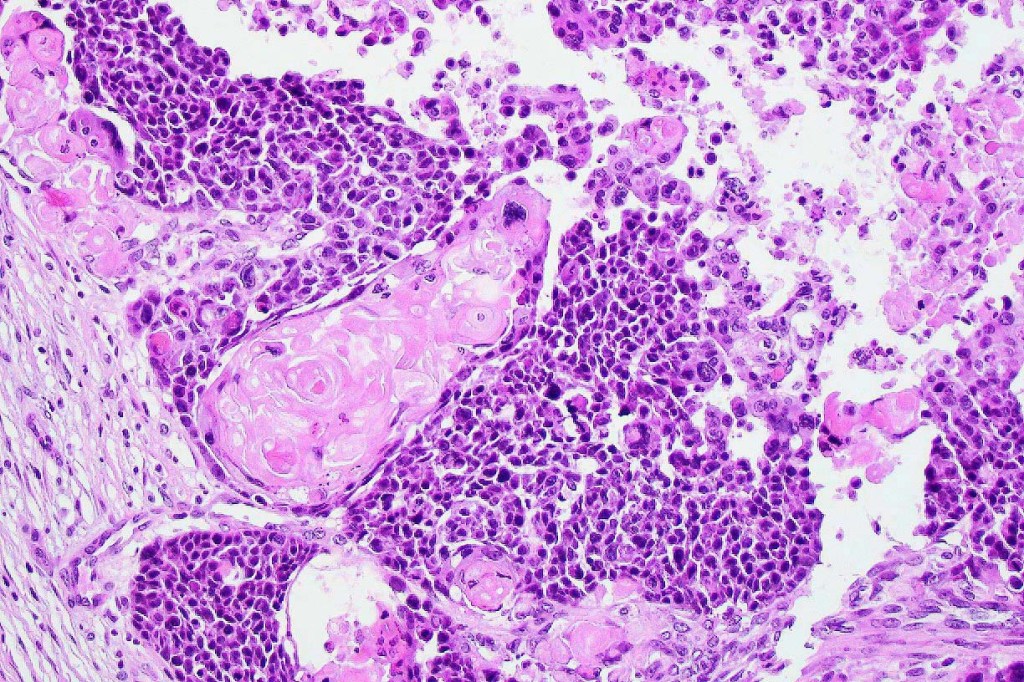

•Lobular or a diffusely infiltrating growth pattern. Composed of pleomorphic hyperchromatic, basaloid cells with nucleolar prominence, abundant mitoses & atypical mitoses (brisk mitotic activity should not be used as a defining feature of matrical carcinoma since in the evolving phase mitoses are typically very numerous in pilomatricoma)

•Necrosis common

•Matricial & supramatricial differentiation

•Squamous differentiation